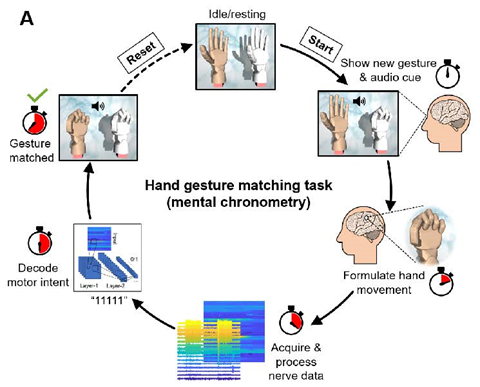

手势匹配任务示意图,测量系统端口之间的反应时间和整个神经接口和运动解码的信息传输率,在每次试验中,受试者看到一个随机的手势,并试图与实时运行的AI神经解码器进行匹配。